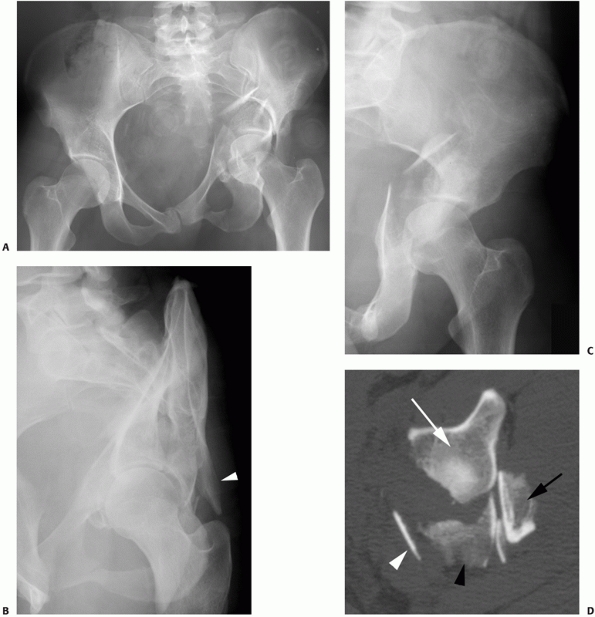

FIGURE 45-30 Radiographic appearance of a both-column fracture. A.

This fracture is unique in that it represents an acetabulum completely

disconnected from the axial skeleton. By definition, all both-column

fractures have no portion of the acetabular articular

surface

remaining attached to the innominate bone and there is a split between

an anterior and a posterior column component. Within this definition,

there is room for many different fracture patterns. In its most simple

form, an anterior column fracture may be associated with a simple

posterior column fracture (see Fig. 45-14).

This is the exception and usually there are secondary fractures

involving the anterior and posterior columns. Even in very comminuted

associated both-column fractures, the acetabular labrum usually remains

intact. Therefore, as the femoral head medializes because of muscular

pull, the articular fragments may each rotate around, yet remain

congruent to, the femoral head (Fig. 45-29). This creates a situation unique to both-column fractures that is known as “secondary congruence.”78,147 The radiograph “spur sign,” when present, is pathognomonic for the associated both-column fracture.78

This is seen best on the obturator oblique projection and represents

the external cortex of the most caudal portion of the intact ilium (Fig. 45-30).

It is generally seen only in the both-column fracture because the

femoral head medializes with all portions of the acetabular articular

surface. The surgeon should recognize that transverse fractures,

transverse and posterior wall fractures, T-shaped fractures, and

anterior/posterior hemitransverse fractures all involve the anterior

and posterior columns of the acetabulum but are not “both-column”

fractures. In these four fracture types, a portion of the articular

surface remains intact with the ilium.78 It is also common for the both-column fracture to have a posterior superior wall fracture component (Figs. 45-30 and 45-31).